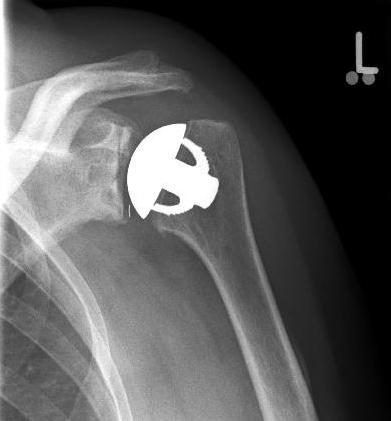

Abbildung11(2)Abbildung11

Fracture prostheses for complicated humeral head fractures

left: X-ray of a humeral head fracture before treatment with a fracture prosthesis.

right: X-ray of a humeral head fracture after treatment with a fracture prosthesis